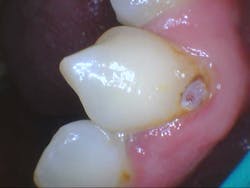

- Additional caries were noted on nos. 10, 11, 14, 26, 27, and 29—primarily facial/buccal caries (figures 3–8)

- In the aforementioned treatment plans, nowhere was it noted or discussed what would happen to the caries on the other teeth aside from nos. 8, 9, and 22.